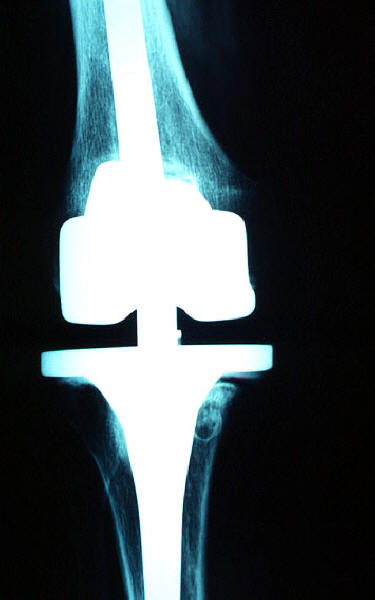

Prótesis completa de rodilla. Situación postquirúrgica.

Prótesis completa de rodilla. Situación postquirúrgica. Lateral.

Prótesis completa de rodilla.Lateral.

Prótesis completa de rodilla. Frontal.